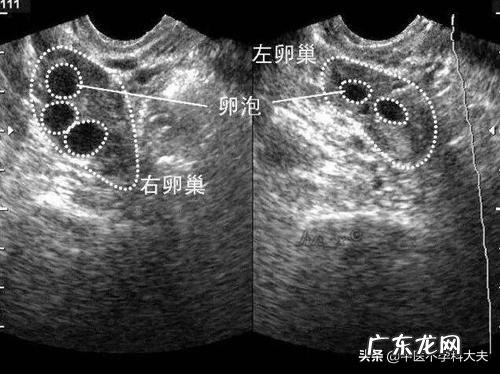

因为这种激素水平不能代表卵泡的质量 , 需要结合卵泡发育的大小以及内分泌激素的情况进行综合的判断 。性激素六项可以反映卵巢分泌雌激素的水平 , 如果水平很低 , 有可能会影响到卵泡的质量 , 会表现出卵泡生长缓慢 , 同时对身体也有一定的影响 。

检查时发现雌二醇低也是内分泌失调的一种表现 , 通常雌二醇低会导致卵巢功能变差 , 间接的影响到卵泡的生长以及发育 。但是往往不能通过雌二醇低就判断卵子的质量不好 , 需要先做一个全面的检查 , 包括B超卵泡检测、性激素六项等 , 以此来判断卵泡的生长发育情况以及找出导致雌二醇低的原因 。